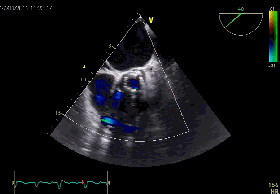

超声评价

超声提示严重MR

释放Clip后反流明显减轻

三维超声下显示二尖瓣呈双孔